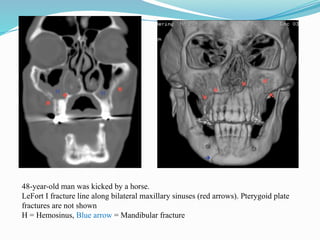

Le Fort I fracture

 Definition: transmaxillary fracture

 Transverse (horizontal) fracture of inferior maxillae, involving maxillary

sinuses (all except superior walls), lateral margin of nasal fossa, nasal

septum and pterygoid plates

 Clinical: free floating and movable hard palate with maxillary teeth

 Imaging findings

 Opacified bilateral maxillary sinuses

 Transverse fracture through the inferior maxillae above hard palate

 Best shown and confirmed by coronal and sagittal reformatted CT images

48-year-old man was kicked by a horse.

LeFort I fracture line along bilateral maxillary sinuses (red arrows). Pterygoid plate

fractures are not shown

H = Hemosinus, Blue arrow = Mandibular fracture